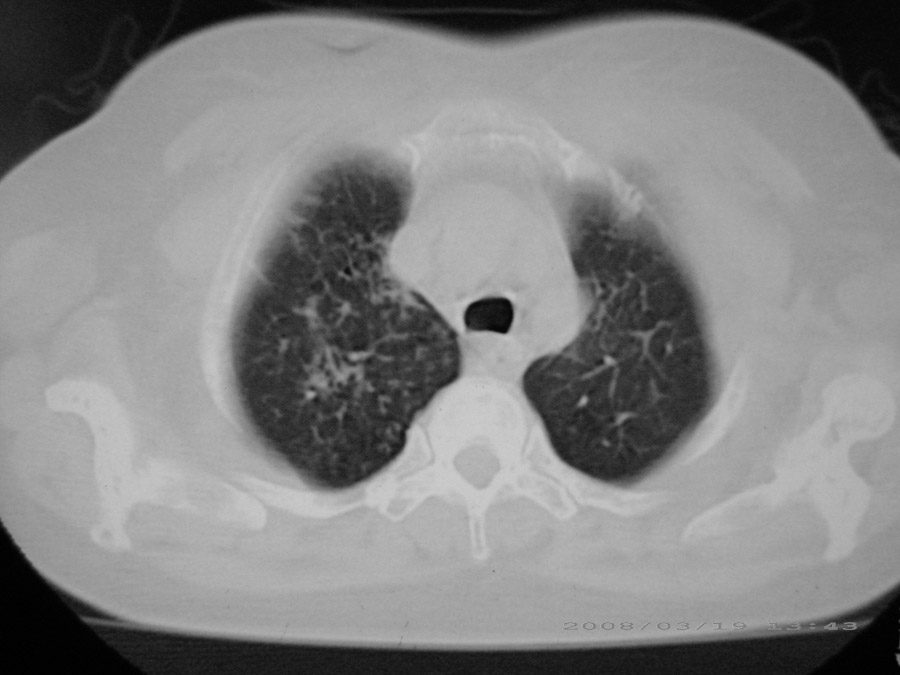

粟粒性结核

细支气管肺泡癌

本病例主要是癌性淋巴管炎与结节病的鉴别。好好查查吧。

密漫性沿纹理走行小结节影;有间质纤维化;可考虑尘肺;以图而论

血行播散性肺结核

两肺间质性病变!考虑间质纤维化?间质性肺炎!

双肺网状结构,小叶间质结节状增厚,考虑结节病

综合大家意见,结核、结节病、肺泡细胞癌均有可能,间质性肺炎暂不考虑,病灶纠集不明显,纵隔未见钙化淋巴结,尘肺可能性不大,但还是要密切结合临床诊断。

今天重新仔细看了看,矽肺确实不能除外,病灶主要表现为间质结节及纤维化。好好问问病史吧。